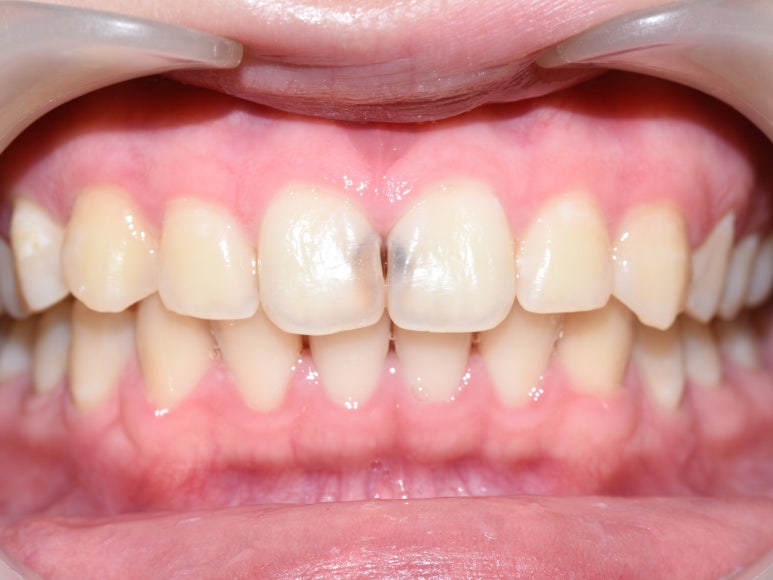

충치제거 후 레진한 치아와, 충치제거 중인 치아

충치제거 후 레진한 치아와, 충치제거 중인 치아의 사진입니다.

충치 제거 후에 레진 충전한 치아는 감쪽 같죠?

어금니는 잘 보이지 않아서 색이 아주 많이 중요하지 않지만

앞니 레진을 위해서는 다양한 색과 쉐이드의 레진이 필요합니다.